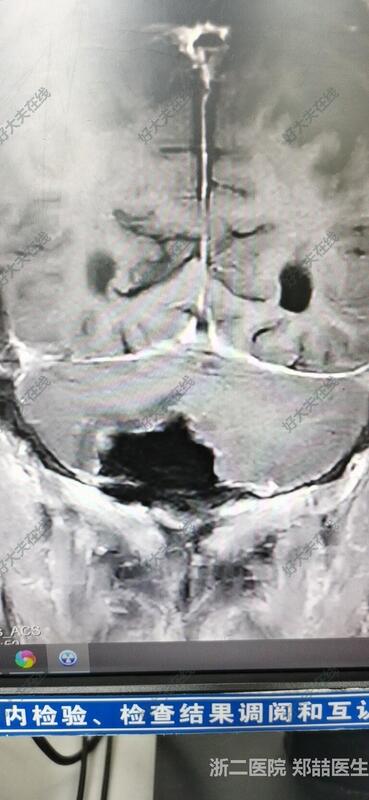

71岁男性,头晕1个月,行走不稳,伴恶心呕吐。头磁共振检查发现后颅窝占位。我院报告淋巴瘤或髓母细胞瘤。个人考虑脑膜瘤可能大,基底广泛。

后正中入路,切除肿瘤,基底广泛,冰冻考虑脑膜瘤。

患者恢复良好,可下地活动,头晕好转,无其他不适。头磁共振复查提示肿瘤全切。